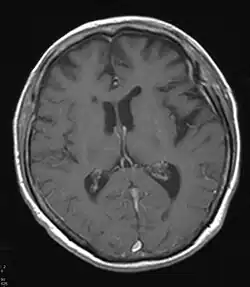

Zugehörige MRT mit entsprechender Atrophie

Neben klinischen Verdachtsmustern kann in vivo eine nuklearmedizinische Diagnostik mit Darstellung der Gehirnperfusion (mit 99mTc-HMPAO) (SPECT) oder des Glucose-Stoffwechsels des Gehirns mit 18FDG (PET) weiterhelfen – typischerweise sind in den Gehirnabschnitten, die dem Krankheitsnamen (frontotemporal) entsprechen, die Durchblutung und der Glucose-Stoffwechsel herabgesetzt.